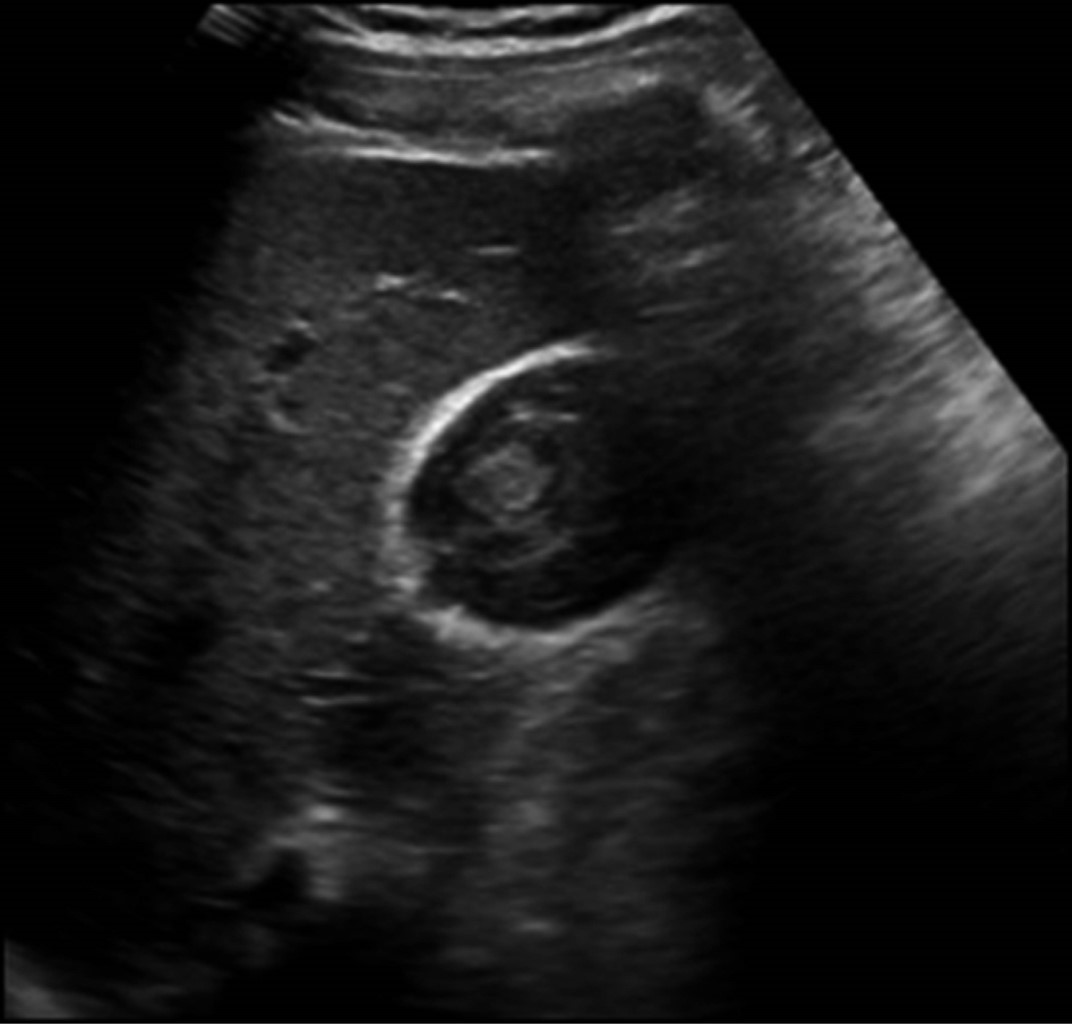

Se decide continuar vigilancia y realizar USG de control a las 27 horas de evolución, en el cual se reportó laceración hepática grado I de la AAST (American Association for the Surgery of Trauma) de 60 mm en su eje longitudinal, y vesícula biliar como se describe en la Figura 2.

Se realiza USG de control que reportó vesícula biliar con paredes engrosadas hasta 8 mm, edema perivesicular, a nivel del fondo pérdida de la continuidad donde discurre líquido de aspecto hipoecoico similar a contenido vesicular de 3.2 cm3 (hemobilia), sin evidencia de líquido libre en cavidad abdominopélvica (Figura 5).